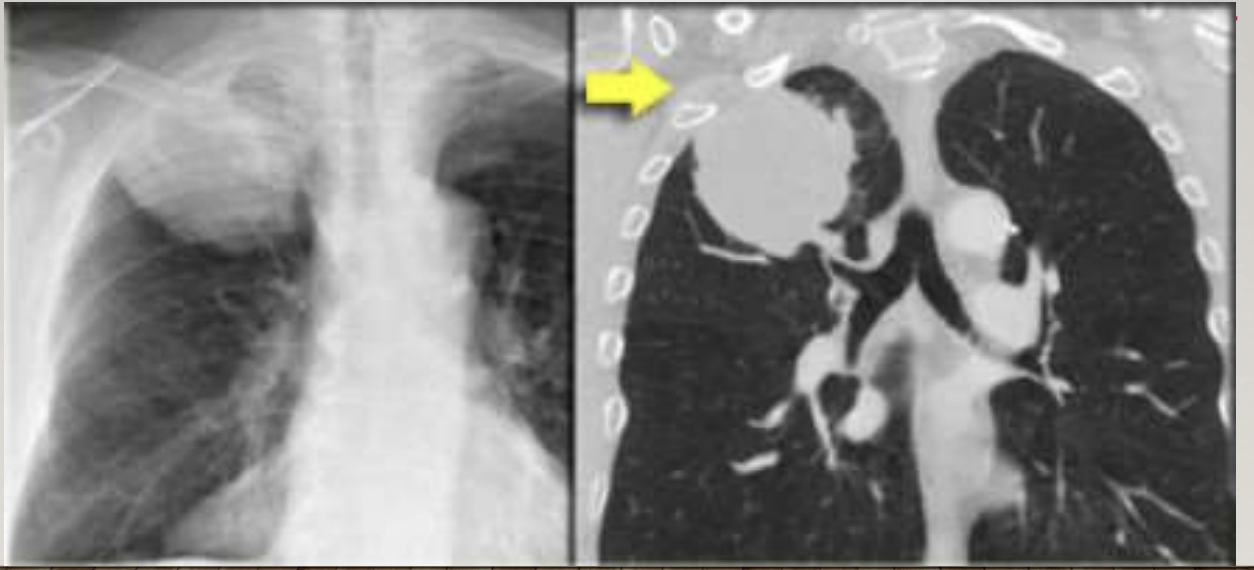

What is shown on the images?

pancoast tumour

pancoast: apical tumour with chest wall pain, Horners syndrome and brachial plexus involvement

an apical lung tumour invading chest wall, brachial plexus and sympathetic chain - causes Horner’s syndrome (ptosis, miosis, anhidrosis) and brachial plexus involvement